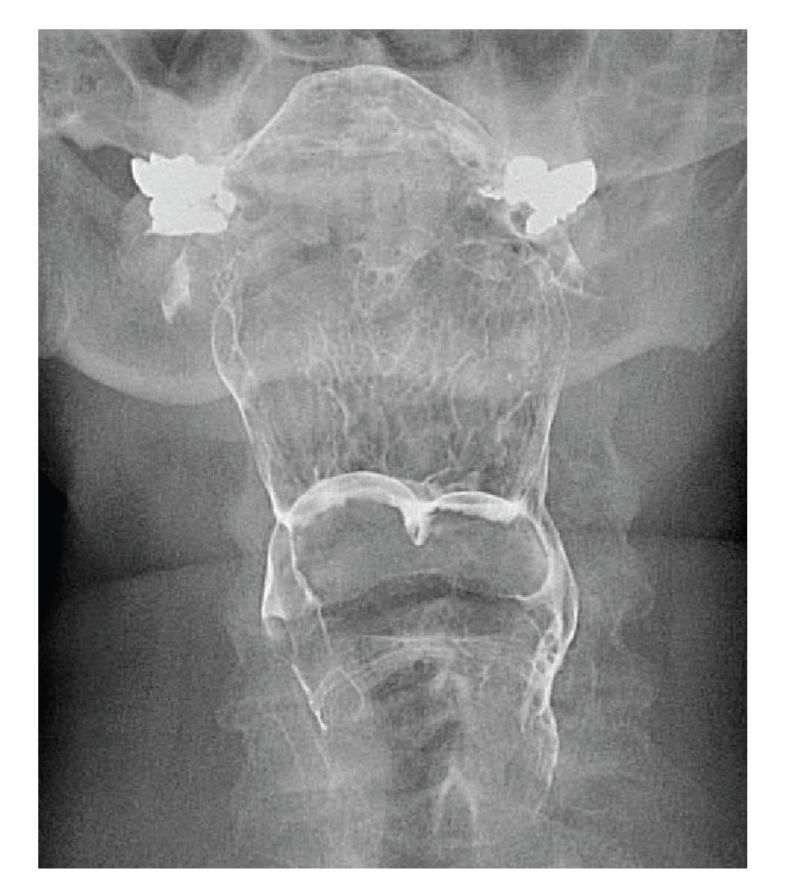

Cysts of the vallecula are rare, accounting for 10.5% to 20.1% of all laryngeal cysts. Vallecular cysts may present with diverse symptoms affecting the voice, airway, and swallowing. We describe the evaluation and treatment of a 70-year-old woman who presented with dysphagia caused by large bilateral vallecular cysts.

会厌谷囊肿罕见,占所有喉囊肿的10.5%至20.1%。会厌谷囊肿可能表现出影响声音、气道和吞咽的多种症状。我们描述了一名70岁女性因双侧巨大会厌谷囊肿导致吞咽困难的评估和治疗情况。